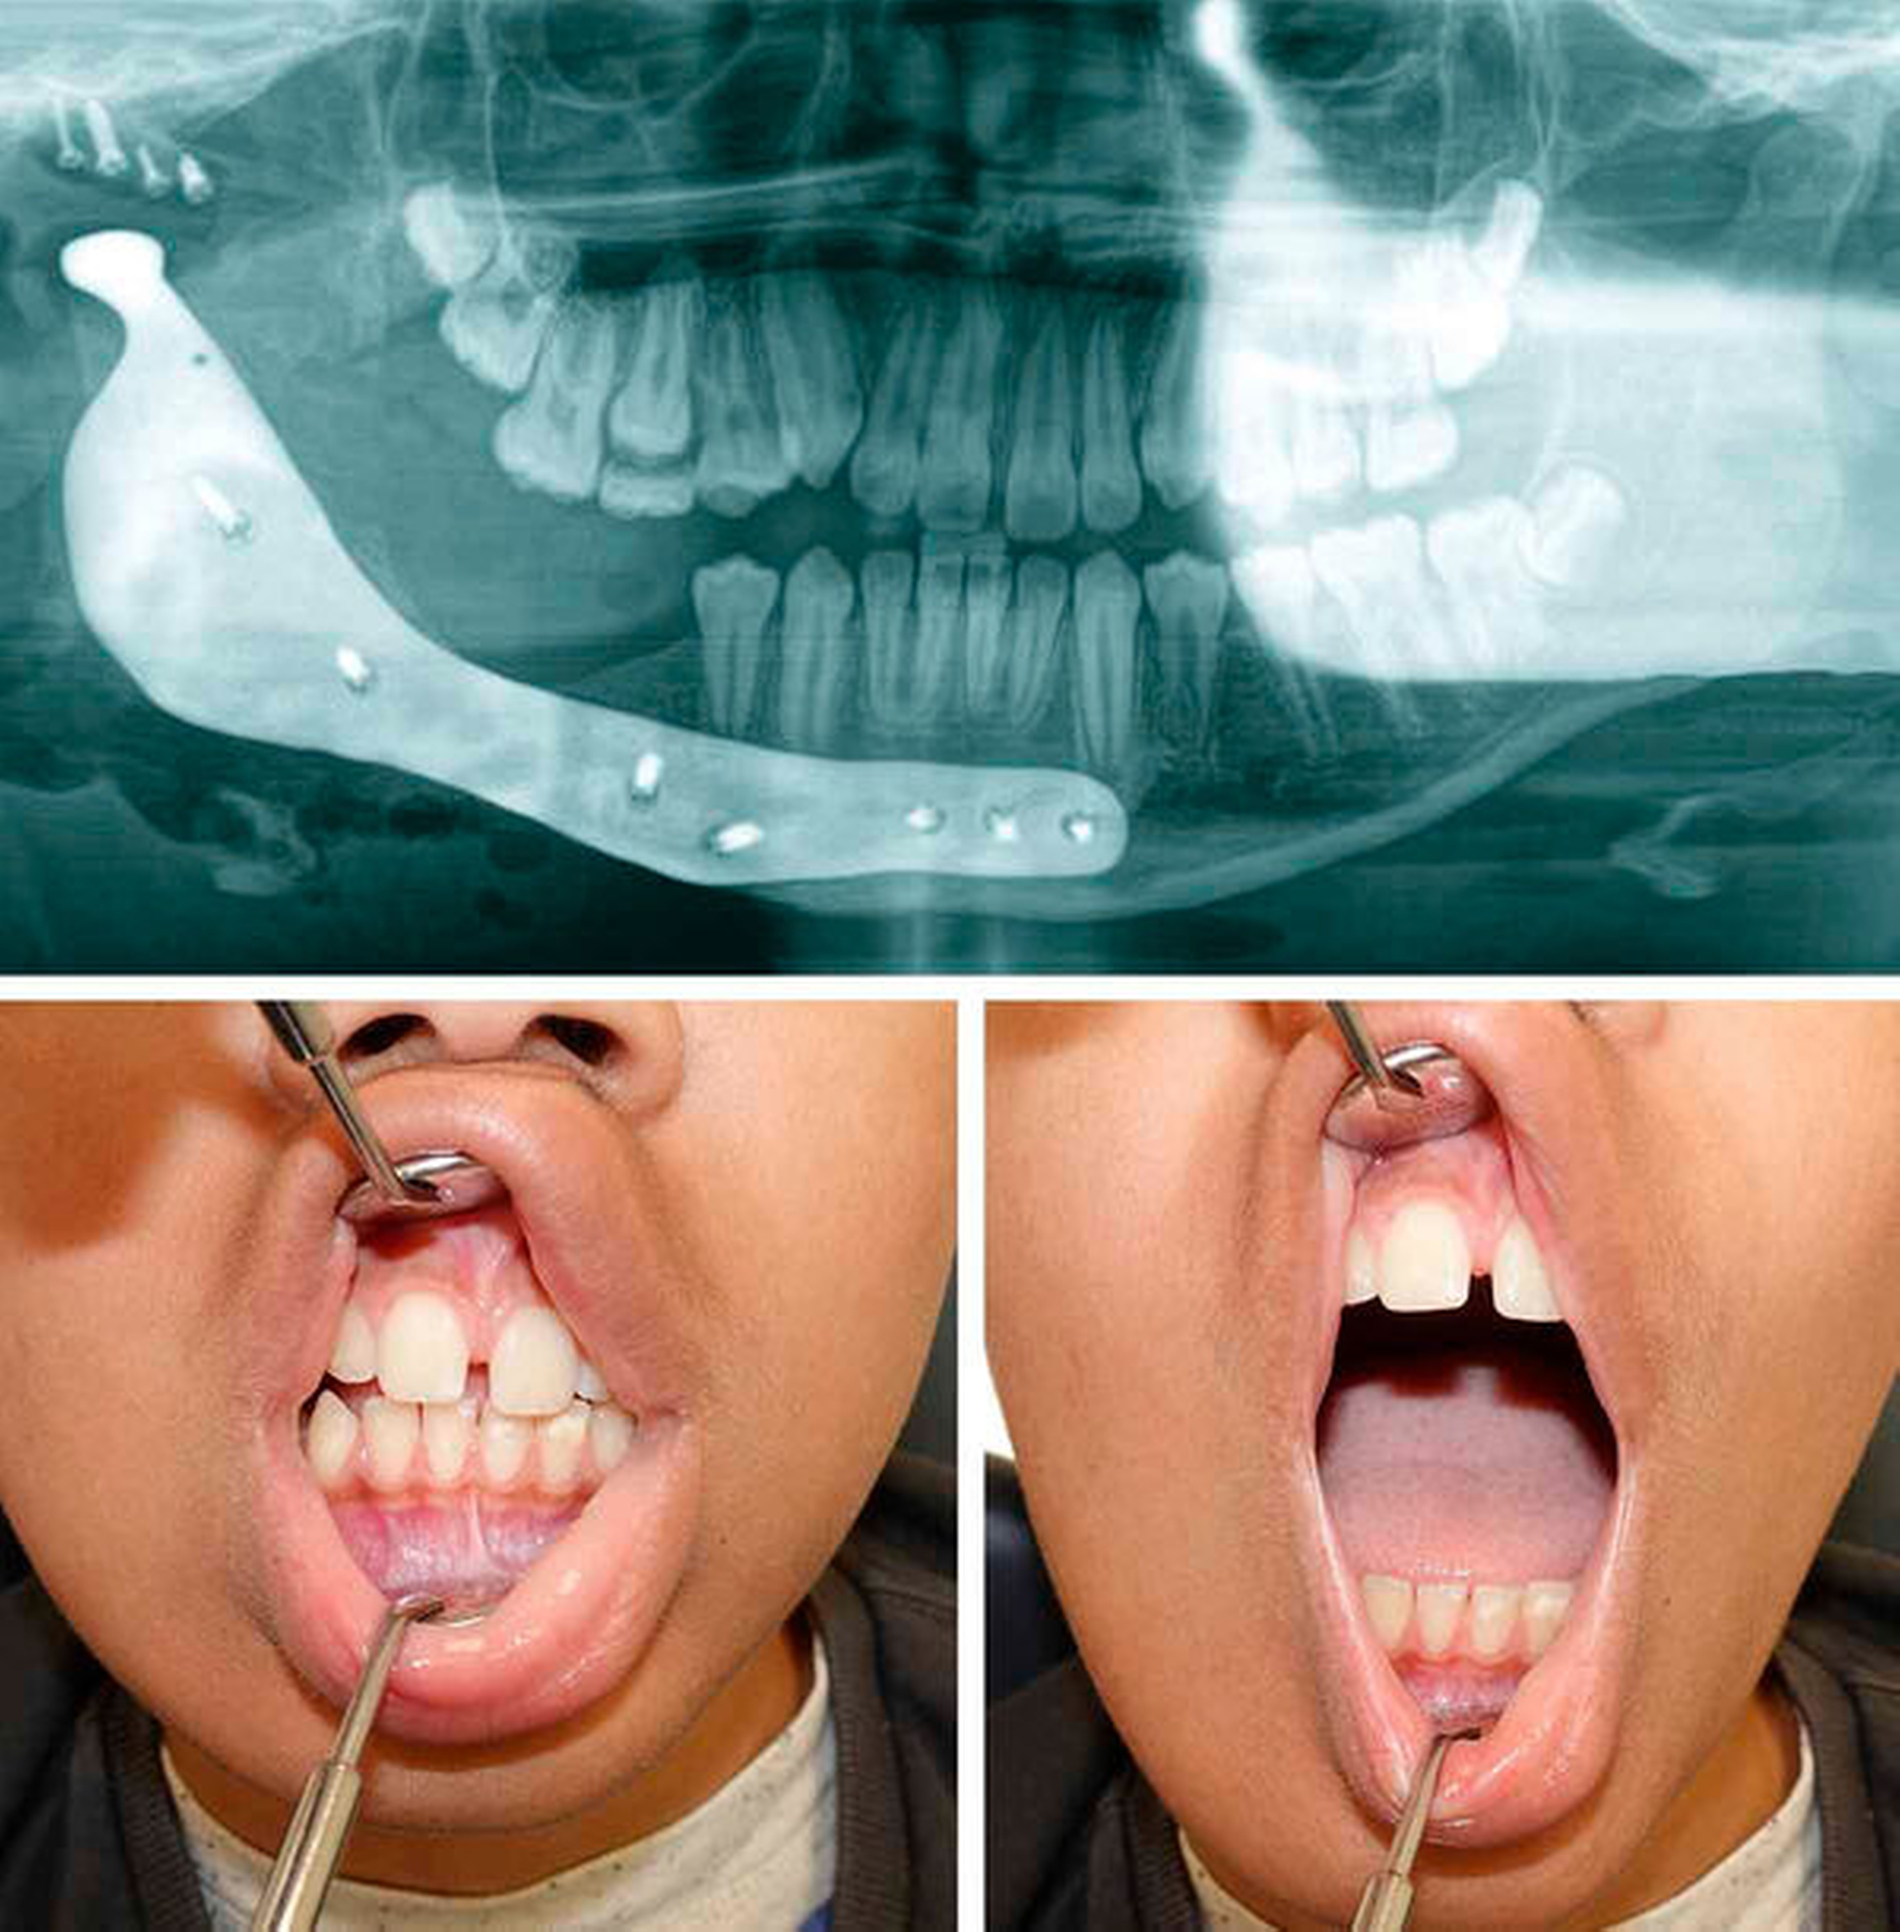

Fünf Monate später erfolgte in einem zweiten Schritt bei einem verlustfrei eingeheilten Beckenkammtransplantat die Entfernung des temporären Kiefergelenkersatzes. Dieser wurde durch eine virtuell geplante und im „computer aided designed / computer aided manufactoring“(CAD/CAM)-Verfahren hergestellte totale Kiefergelenkendoprothese (TEP) ersetzt. Die Kiefergelenkpfanne aus hochverdichtetem und abriebfestem Polyethylen (ultra-high molecular weight polyethylene, UHMWPE) wurde als Onlay über der knöchernen Pfanne positioniert und verschraubt. Das Kondylen-tragende Segment aus einer Kobalt-Chrom-Titan-Nickel-Legierung umfasste das Beckenkammtransplantat, die ipsilaterale Mandibula und – aus Stabilitätsgründen – auch den kontralateralen anterioren Mandibulabereich (Abbildung 4). Bereits drei Monate postoperativ zeigte sich bei einer nach wie vor habituellen Okklusion eine normale maximale Mundöffnung von 40 mm SKD (Abbildung 5).

Ein Jahr nach Erstdiagnose ergaben sich keine Hinweise auf ein Rezidiv, Wachstumsstörungen oder eine Funktionsstörung der TEP. Der junge Patient hatte sich gut an den Sensibilitätsausfall der Lippen- und der Kinnregion adaptiert und berichtete zu diesem Zeitpunkt sogar über wieder vorhandenes Empfindungsvermögen.